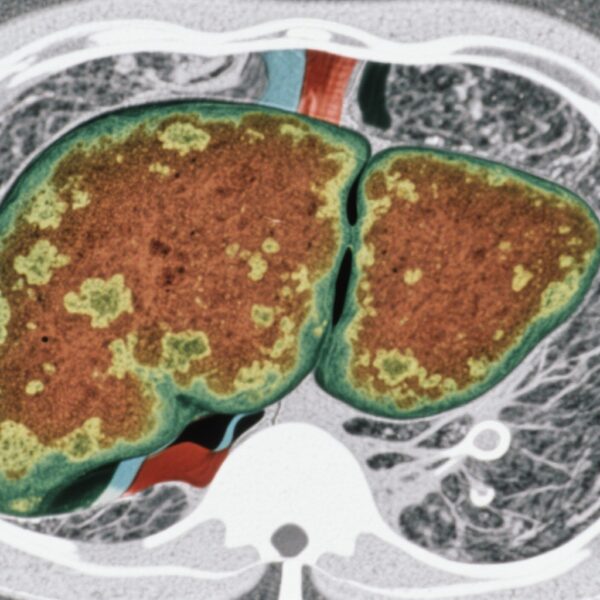

Ung thư đường mật (BTC) bao gồm một nhóm đa dạng các khối u ác tính xuất phát từ niêm mạc đường mật, bao gồm cả cholangiocarcinoma nội gan và ngoại gan cũng như ung thư túi mật. Mặc dù tỷ lệ mắc bệnh thấp hơn so với các bệnh ung thư tiêu hóa khác, BTC có tiên lượng xấu, với phần lớn bệnh nhân được chẩn đoán ở giai đoạn tiến triển, nơi các lựa chọn điều trị triệt để bị hạn chế. Thời gian sống trung bình (OS) trong BTC tiến triển vẫn rất kém bất chấp các liệu pháp hệ thống, làm nổi bật nhu cầu cấp bách về các phương pháp điều trị hiệu quả.